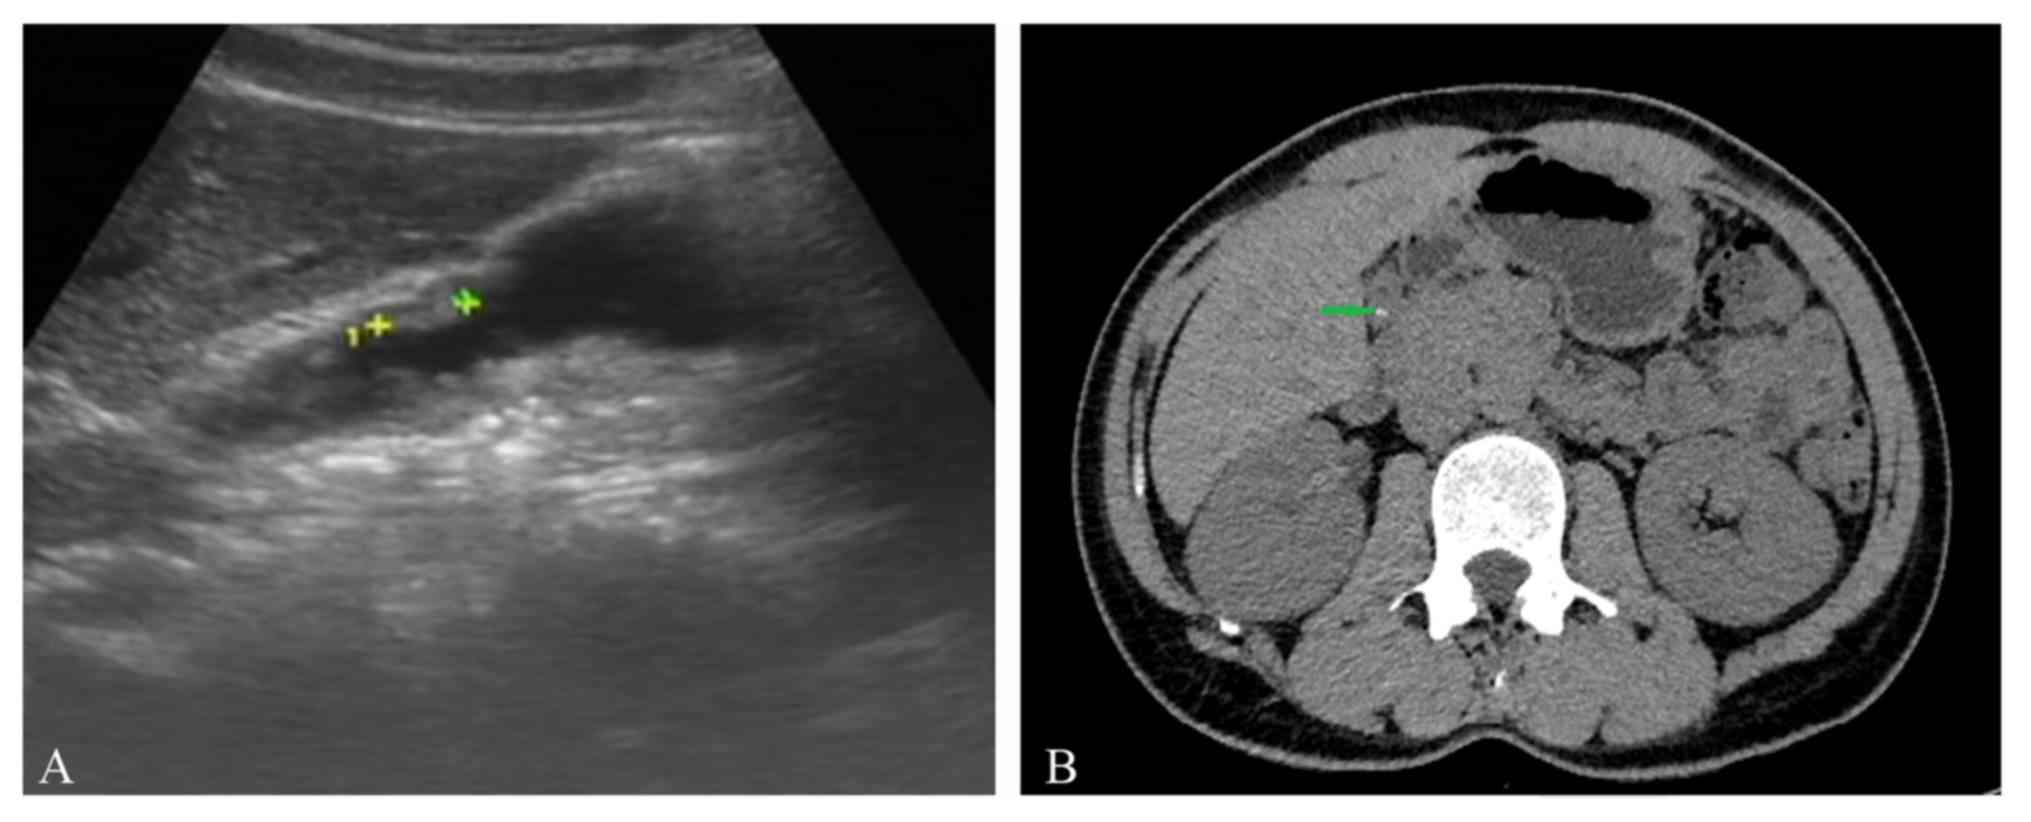

A 45-year-old male patient presented at the Affiliated Hospital of Nanjing Medical University of Traditional Chinese Medicine (Nanjing, China) in May, 2018 and requested the removal of his cholecystic polyps and cholecystolithiasis which had been diagnosed earlier in the outpatient department of the hospital with preservation of the gallbladder. Over the past 2 years, the patient had experienced frequent abdominal pain and fever. Cholecystic polyps and gallstones were observed by pre-operative abdominal ultrasonography (Fig. 1A) and abdominal CT (Fig. 1B). It was estimated that the maximum diameter of cholecystic polyps was 1.2 cm and that of the biggest stone was 0.8 cm. The pre-operative gallbladder ejection function was deemed good according to gallbladder contraction function test under abdominal ultrasound. Following consultation of relevant literature and discussion with certain endoscopy experts, it was decided that transgastric endoscopic gallbladder polypectomy and cholecystolithiasis was feasible in this patient (10–12). The present study reports on the successful use of flexible transgastric endoscopy in gallbladder polypectomy and treating cholecystolithiasis, which appears to be a promising novel surgical option for patients wishing to retain their gallbladder and functions without scarring on the abdominal wall. Prior to the operation, written informed consent was obtained from the patient and the operation was approved by written the Ethics Committee of Affiliated Hospital of Nanjing University of Chinese Medicine (Nanjing, China).

Figure 1.

(A) Pre-operative abdominal ultrasonography was performed. The maximum diameter of the cholecystic polyps was 1.2 cm (indicated between green ‘+’ and yellow ‘+’ symbol). (B) Gallstones were observed by pre-operative abdominal CT (green arrow).